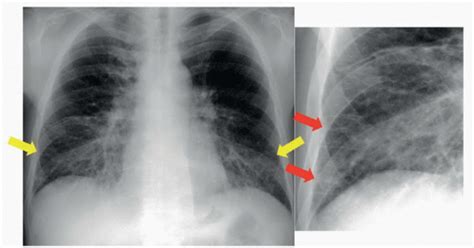

So, how do doctors diagnose and treat these pulmonary and interstitial issues? Well, the process usually starts with a thorough medical history and physical exam. Your doctor will ask about your symptoms, past illnesses, and any exposures that might be relevant (like smoking or exposure to asbestos). They’ll also listen to your lungs with a stethoscope to check for any abnormal sounds, like wheezing or crackles. If they suspect a pulmonary or interstitial problem, they’ll likely order some imaging tests. A chest X-ray is often the first step, as it can help identify obvious abnormalities like infections or tumors. However, for a more detailed look, a high-resolution CT scan is usually necessary. This can provide a much clearer picture of the lungs and help identify subtle changes in the interstitium. Pulmonary function tests are also crucial. These tests measure how much air you can inhale and exhale, and how quickly you can move air in and out of your lungs. They can help determine the severity of any pulmonary or interstitial disease and track its progression over time. In some cases, a lung biopsy may be needed to make a definitive diagnosis. This involves taking a small sample of lung tissue for examination under a microscope. As for treatment, it really depends on the specific condition. For infections, antibiotics or antiviral medications may be used. For obstructive diseases like COPD and asthma, bronchodilators and inhaled corticosteroids can help open up the airways and reduce inflammation. For interstitial lung diseases, medications that suppress the immune system or reduce inflammation may be prescribed. Pulmonary rehabilitation, which includes exercise training and education, can also be very helpful for improving lung function and quality of life. And in some cases, oxygen therapy may be needed to help maintain adequate oxygen levels in the blood.